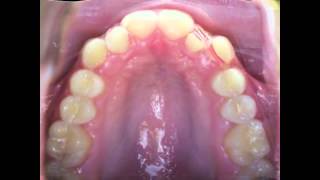

Orthodontic Treatment For Narrow Upper Jaw With...

2.038.343

1:01

Braces Time Lapse, Before And After, Maxillary...

11.314

0:27